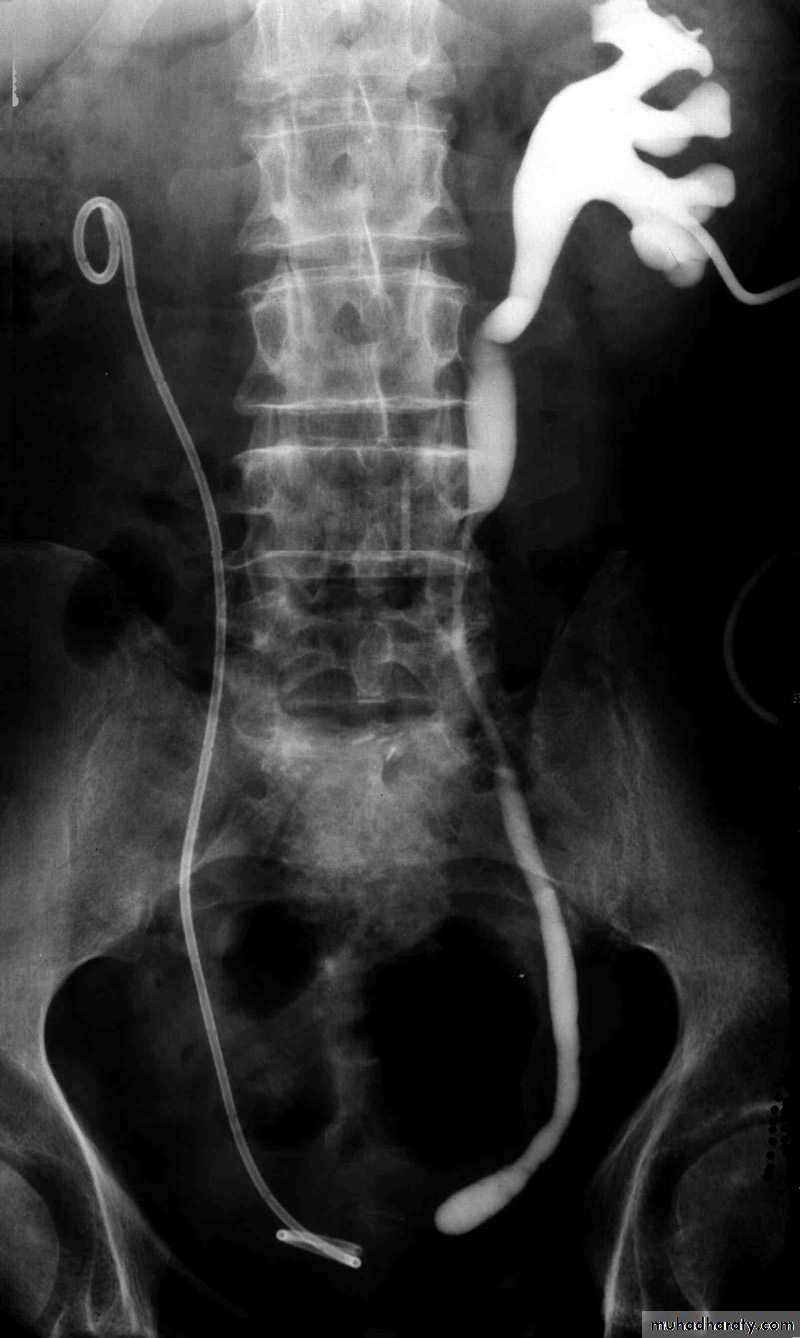

Postcaval (Retrocaval) ureter (Preureteral Vena Cava )

The right ureter pass behind the inferior vena cavaThis might causes obstruction

It is a vascular abnormality

Diagnosis: IVU

Treatment

surgical correction involves ureteral division, with relocation and ureteroureteral or ureteropelvic reanastomosis, usually with excision or bypass of the retrocaval segment, which can be aperistaltic